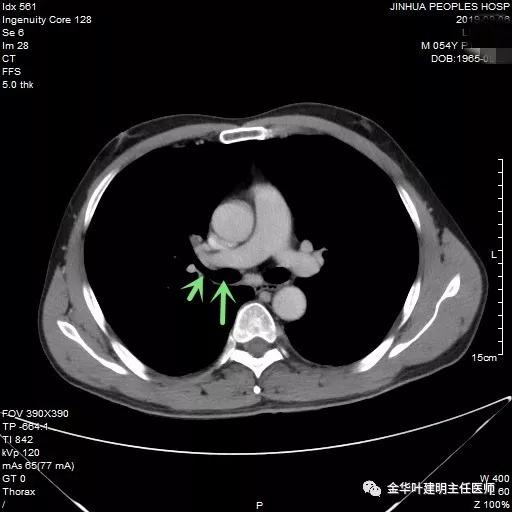

可见右中间支气管开口处新生物,堵塞管腔,明显是肿瘤,但因当时服用波立维与阿斯匹林双抗治疗,停的时间还不够,所以没有活检,而刷检没找到癌细胞。请我会诊时,我看了李某的胸部CT增强:

上图示上叶支气管通畅

上图示中间支气管起始处似乎还算正常